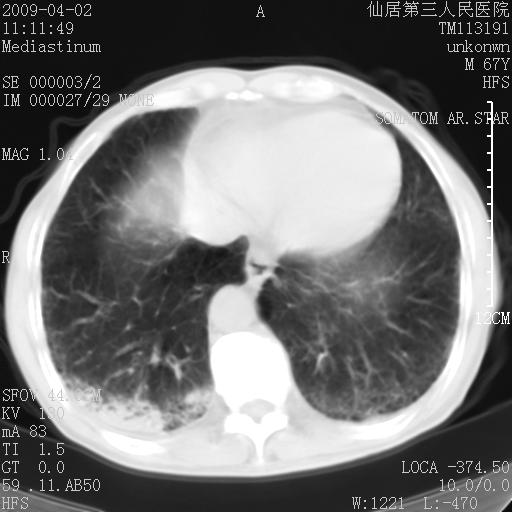

患者老年男性,乏力畏寒来诊,摄胸片示右下肺感染性病变,抗炎两周后复查胸片,无好转有进展。

后做ct平扫表现如下:

考虑右肺炎症可能性大,不除外细支气管肺泡癌

是否还要考虑肺间质纤维化,建议hrct扫描。

病灶呈蜂窝征,纵隔多个淋巴结肿大;肺泡癌需考虑

右肺下叶背段干酪性肺炎。请痰检[emb28]

考虑双肺间质性改变(间质纤维化?)伴右肺下叶感染。